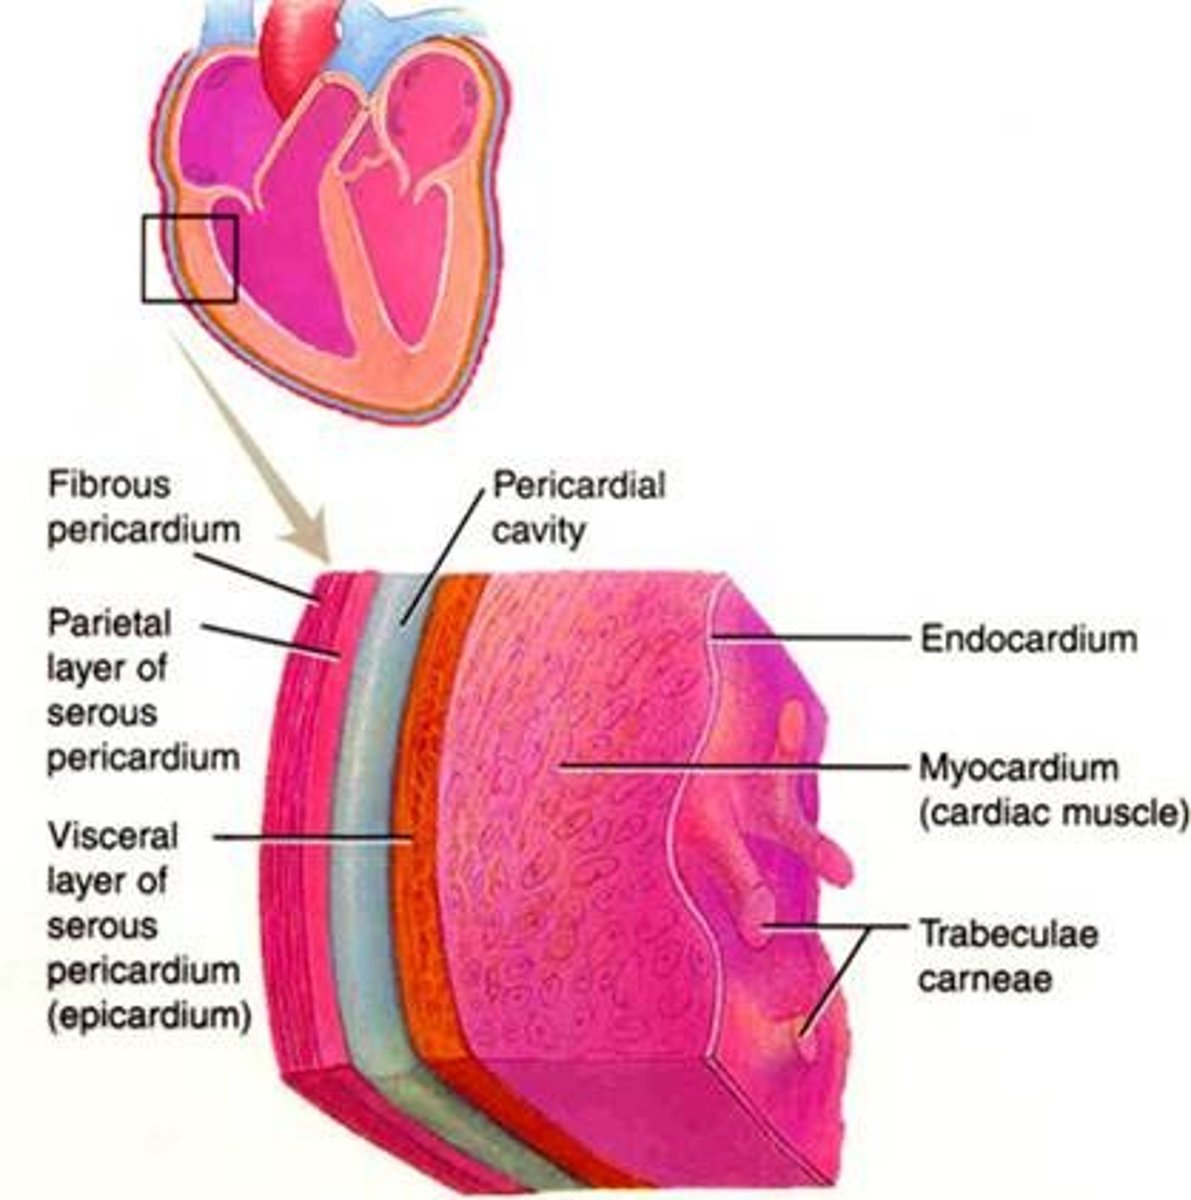

Jakie rodzaje osierdzia wyróżniamy?

surowicze i włókniste

osierdzie surowicze

serous pericardium

Z jakich części składa się osierdzie surowicze?

z blaszki trzewnej i ściennej

blaszka trzewna osierdzia surowiczego

visceral layer of serous pericardium

blaszka trzewna osierdzia surowiczego inaczej

nasierdzie

nasierdzie

epicardium

blaszka ścienna osierdzia surowiczego

parietal layer of serous pericardium

Gdzie znajduje się jama osierdzia?

między blaszką ścienną i trzewną osierdzia surowiczego

jama osierdzia

pericardial cavity

Jak jest położone nasierdzie?

ściśle zrośnięte z powierzchnią zewnętrzną serca

Co pokrywa nasierdzie?

tętnice wieńcowe i żż. serca

aortę wstępującą

pień płucny

końcowy odcinek ż. głównej górnej

Jak odróżnić blaszkę ścienną osierdzia surowiczego i osierdzie włókniste?

Nie da się - są ze sobą zrośnięte

Co znajduje się w jamie osierdzia?

płyn surowiczy umożliwiający ślizganie się blaszek osierdzia

osierdzie włókniste

fibrous pericardium

Co otacza osierdzie włókniste?

od zewnątrz osierdzie surowicze